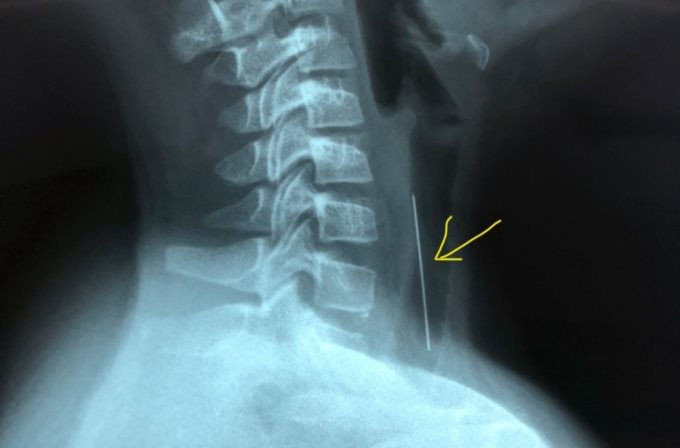

Bệnh viện Nhi Đồng 1 vừa tiếp nhận một bệnh nhi 10 tuổi, ngậm cây kim dài hơn 4cm, có một đầu gắn nhựa lỡ nuốt xuống họng.

Bé trai VQ. bị đau vùng cổ, dù cố ho khạc nhưng không lấy được kim ra ngoài. Chụp X-quang tại bệnh viện địa phương, các bác sĩ chẩn đoán có dị vật ở khí quản nên chuyển bé đến Bệnh viện Nhi đồng 1, TPHCM xử trí.

Bệnh nhi được chỉ định gây mê nội soi đường thở gắp dị vật. Lúc này, đầu kim nhọn đang quay lên phía trên, đâm sâu hơn 1cm vào thành khí quản.